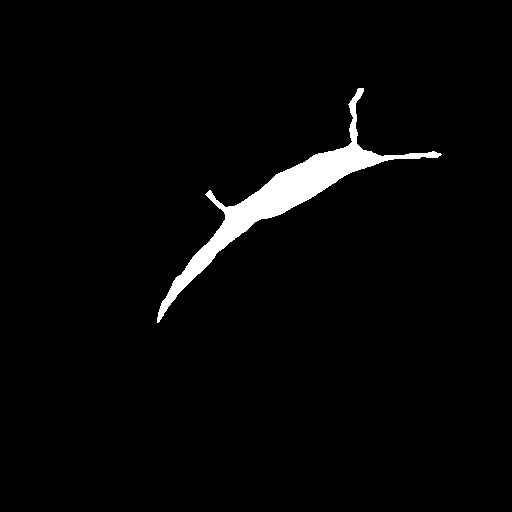

Raw

GT

AURA-net

3.5 Failure Cases

In Figure 3, we illustrate failure cases in dataset . In the first example, AURA-net fails to correctly segment the bottom part of the object. This outcome is unsurprising considering that the raw image exhibits a lower SNR than any of the training data. In the second example, the segmentation mask predicted by AURA-net contains several objects, yielding a poor overlap with the ground truth annotation featuring a single cell. However, the original image reveals the presence of a second, partially cropped non-annotated cell. In this case, part of AURA-net’s “false” detection are actually correct predictions that have been omitted in ground truth annotations.